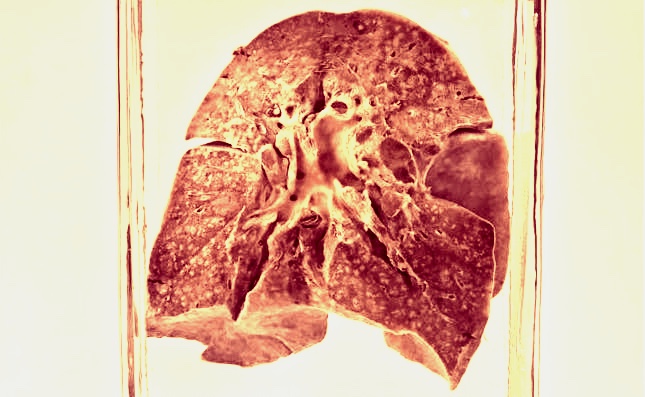

The lungs were originally collected during an autopsy after their original owner died of measles-related bronchopneumonia on June 3, 1912, according to the paper’s supplementary material. Then, they remained untouched for over a century.

As Science magazine reported, these lungs were found by the study’s senior author Sébastien Calvignac-Spencer in a basement at the Berlin Museum of Medical History. That museum is already known for a collection of organs suspended in jars, reminiscent of Snape’s potion classroom.